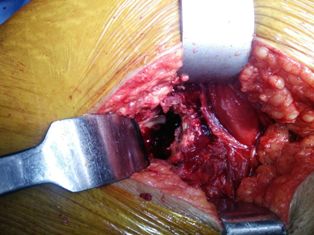

Procedure : THR (Total Hip Replacement) left side done

• A case of neglected fracture.

• Fracture dislocation of Hip joint.

• Plan (THR) Total HIP Replacement while Acetabulum Exposure there is no wall on superior and posterior aspect, Central Wall also absent.

• Having no option, decided to put cage in the Acetabulum and done cemented Total Hip Replacement.